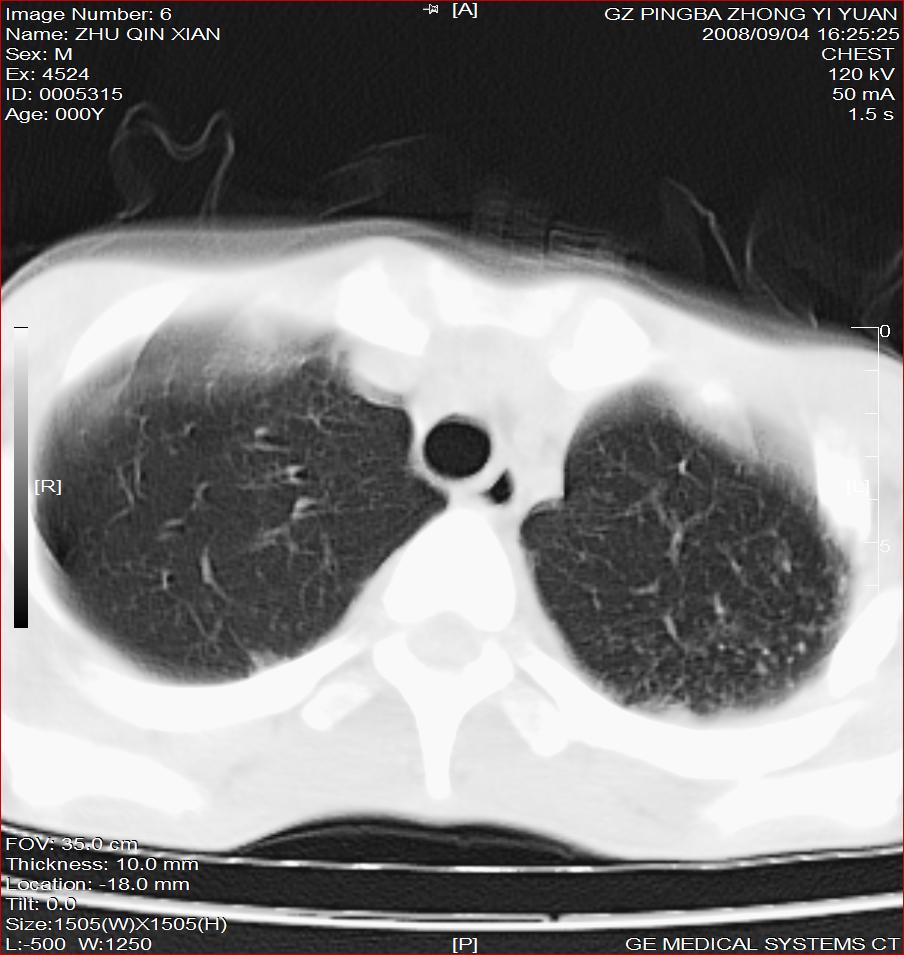

以下是引用随光逐影在2008-9-4 20:05:00的发言:[br]1)考虑两肺结核。2)左侧胸膜炎(胸膜肥厚、粘连,胸腔积液)。3)左侧局限性气胸。

以下是引用子十在2008-9-4 19:34:00的发言:[br]左上肺结核并空洞及双肺播散。节段性肺不张、胸腔积液、胸膜肥厚粘连。[br]